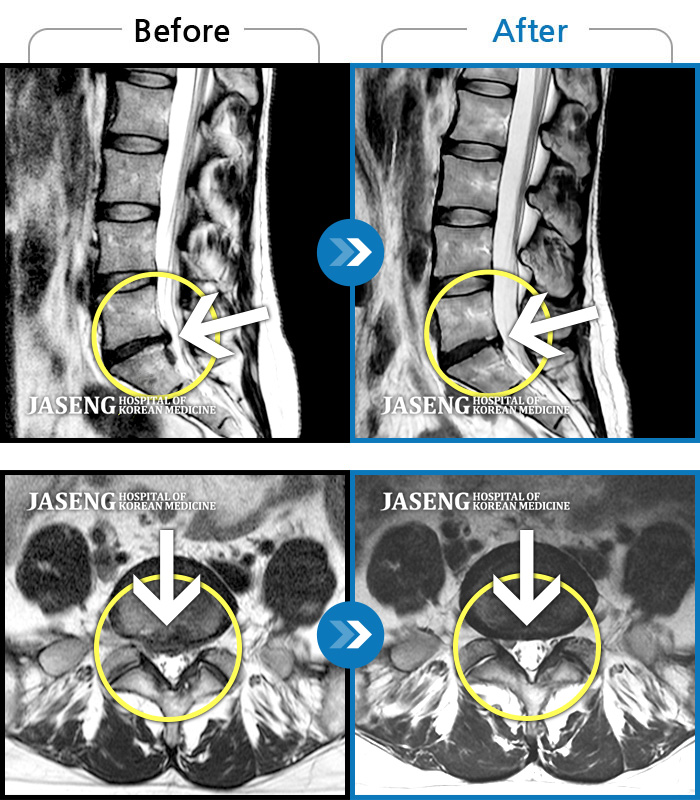

[뱸] 19.11.28~25.05.06

ȯںп Ǹ ǿ ԿǾ, ο ġ ۿ Ƿ ġḦ Ͻñ ٶϴ.